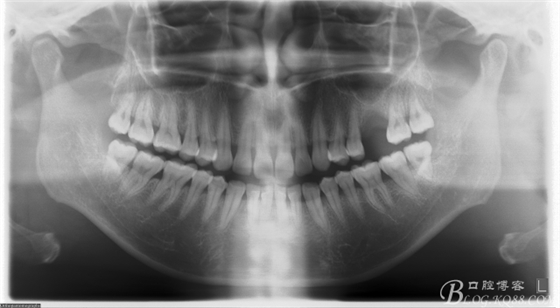

術(shù)前X片。上頜竇外提一例